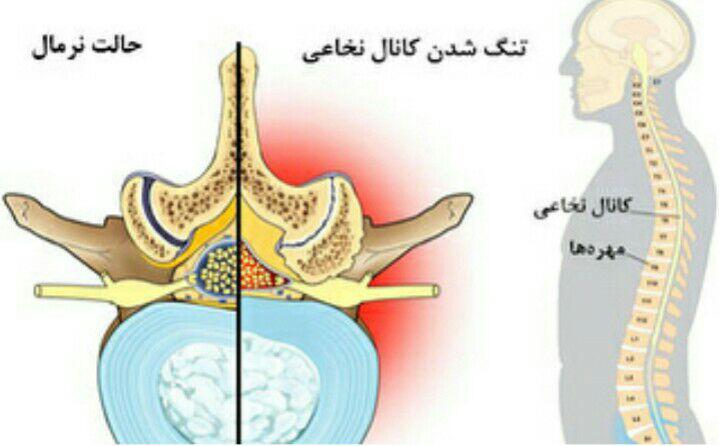

-درمان تنگی کانال نخاعی غیرقابل جراحی

دردهای اسکلتی عضلانی (کمردرد، گردندرد، زانودرد، آرتروز)

دردهای عصبی (سیاتیک، نوروپاتی دیابتی، نورالژی پس از زونا)